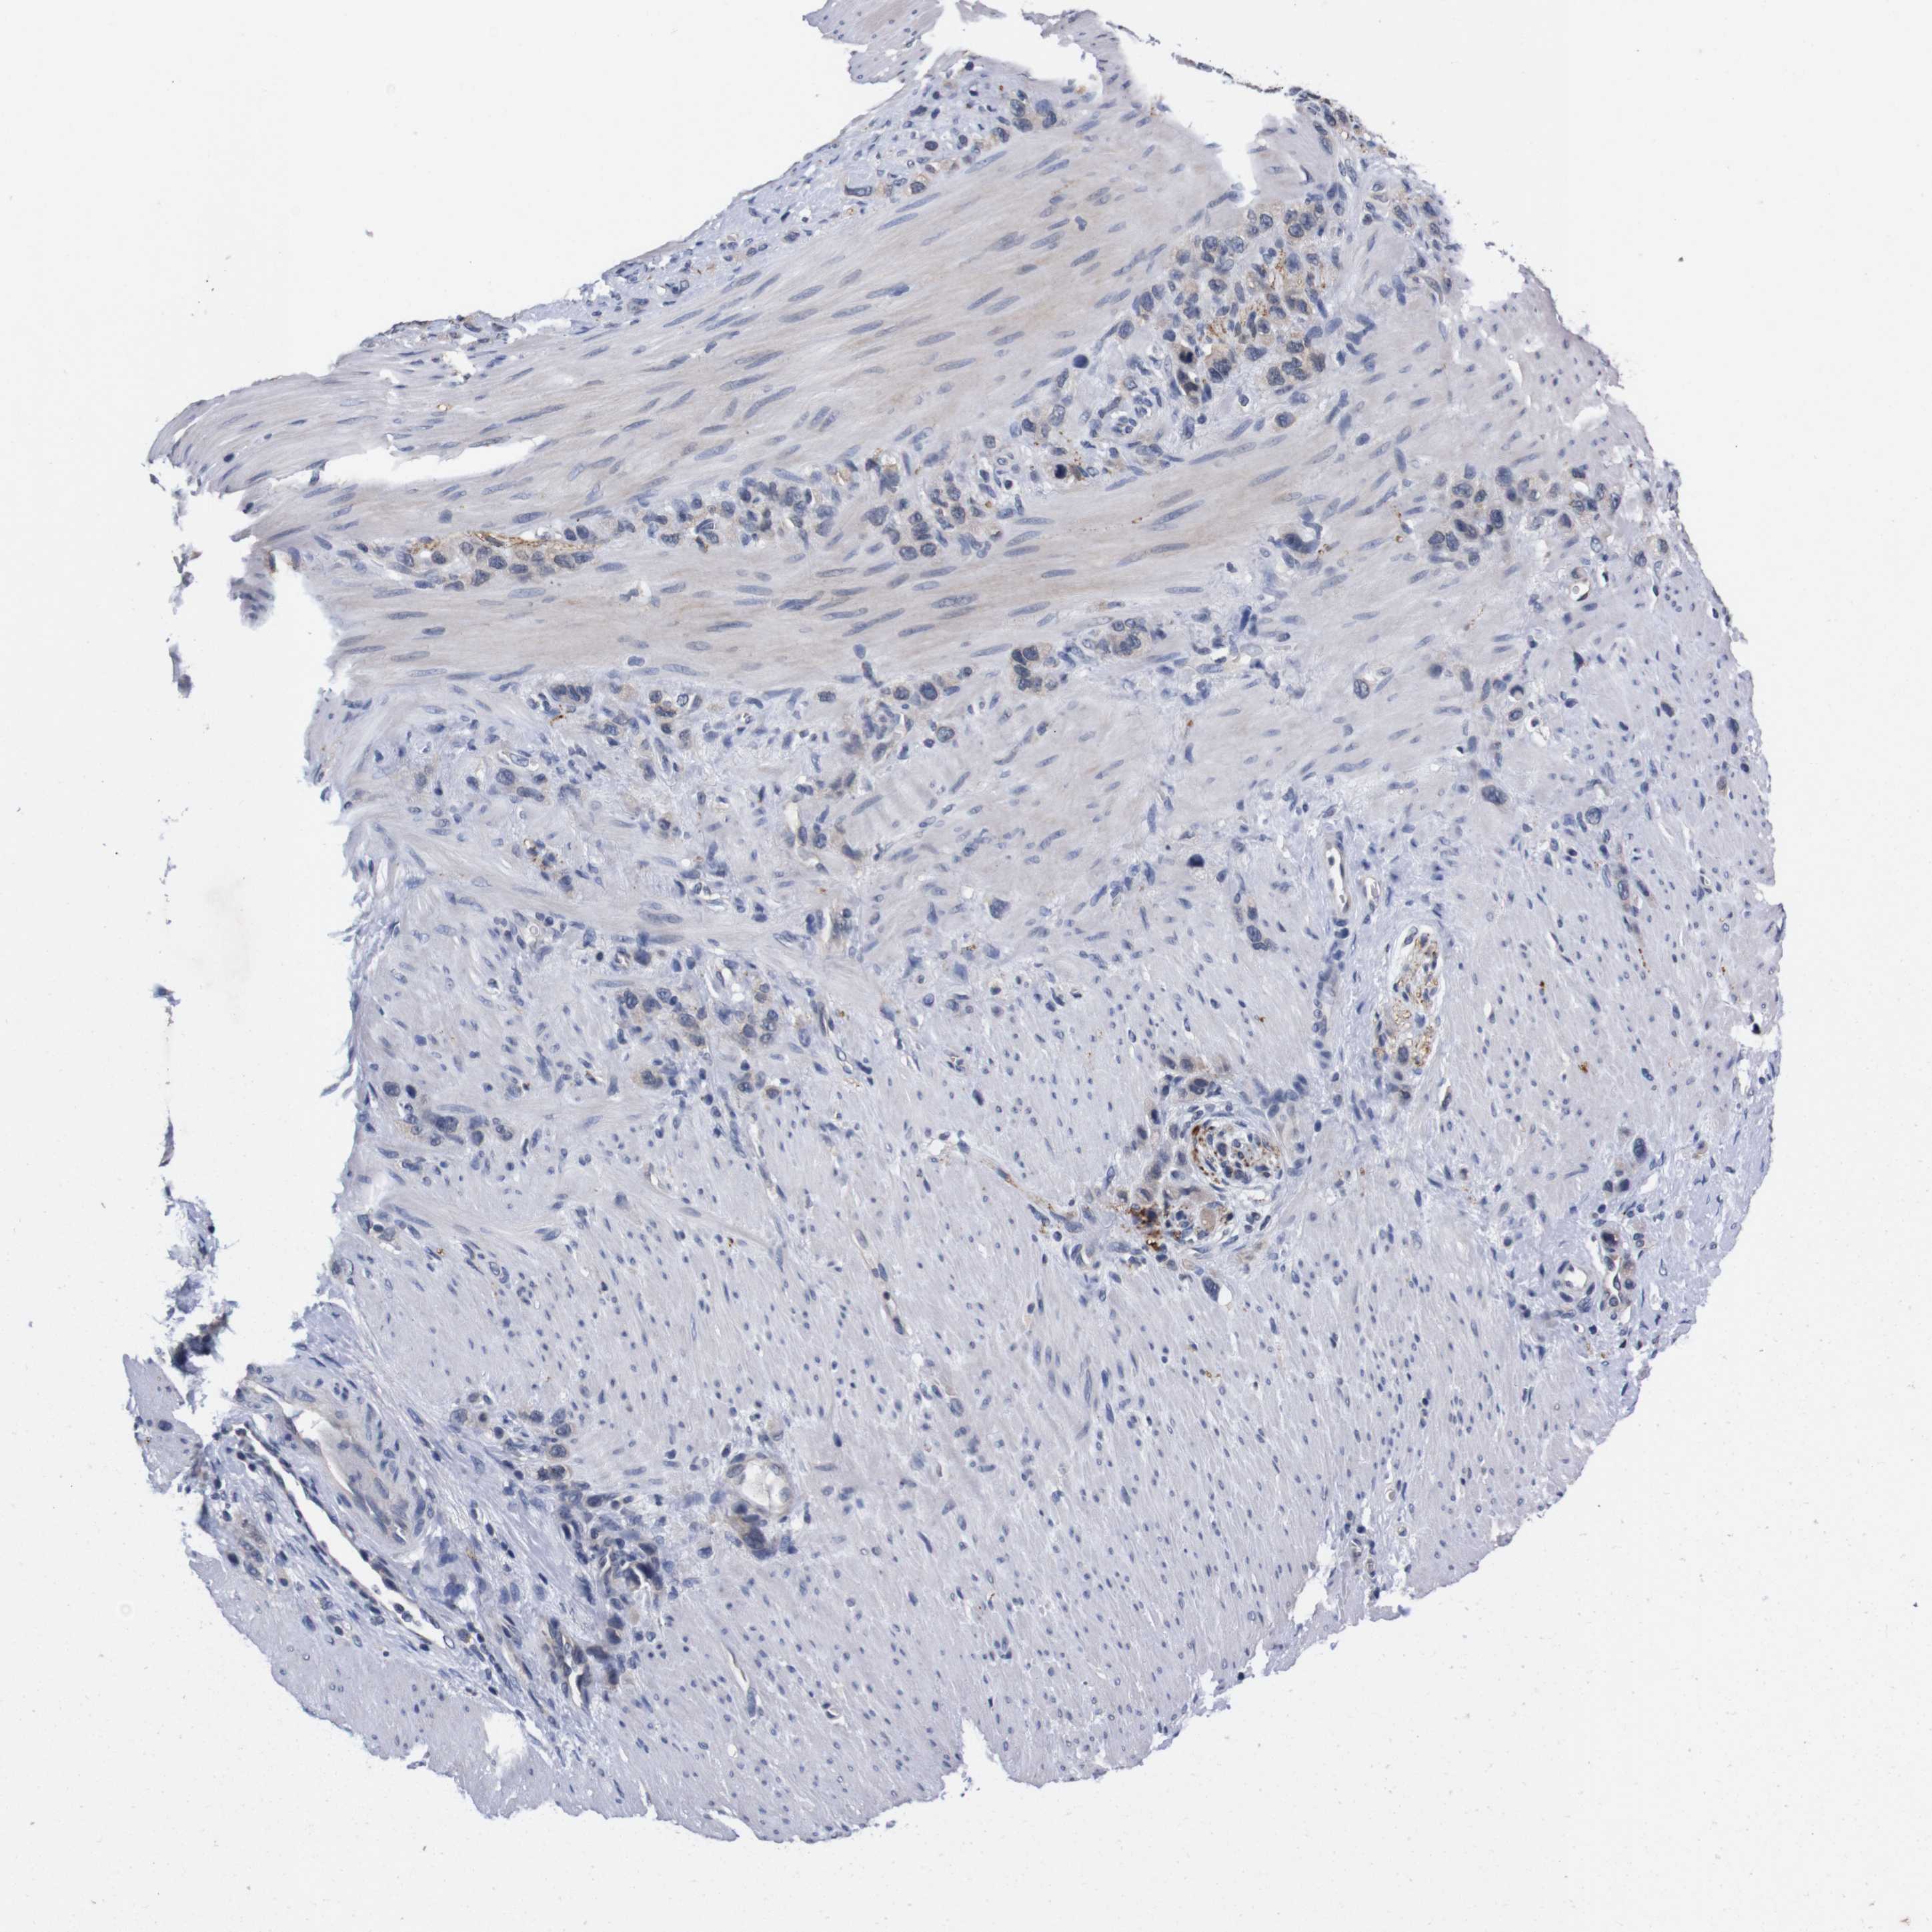

STOMACH CANCER - Protein expressioni

A mouse-over function shows sample information and annotation data. Click on an image to view it in a full screen mode. Samples can be filtered based on level of antibody staining by selecting one or several of the following categories: high, medium, low and not detected. The assay and annotation is described here.

Antibody stainingi

Antibody staining in the annotated cell types in the current human tissue is reported as not detected, low, medium, or high, based on conventional immunohistochemistry profiling in selected tissues. This score is based on the combination of the staining intensity and fraction of stained cells.

Each image is clickable and will lead to virtual microscopy that enables deeper exploration of all samples and also displays staining intensity scores, fraction scores and subcellular localization as well as patient and tissue information for each sample.

Antibody HPA006746

Antibody CAB009805

Staining

High

Medium

Low

Not detected

Intensity

Strong

Moderate

Weak

Negative

Quantity

>75%

75%-25%

<25%

None

Location

Nuclear

Cytoplasmic/membranous

Cytoplasmic/membranous,nuclear

Adenocarcinoma, NOS

Adenocarcinoma, High grade